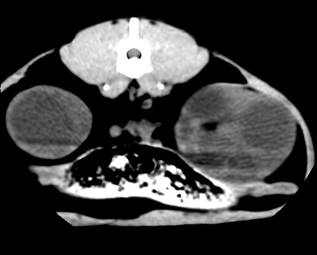

Комп’ютерна томографія нирок у домашніх собак

і кішок,

хворих на полікистоз. Враховуючи той факт, що в

доступній спеціальній літературі не вдалося знайти повідомлень щодо

застосування методу комп’ютерної томографії для діагностики ренальних патологій

у кішок, ми у своїй роботі вважали актуальним вивчення цього питання.

Комп’ютерну томографію застосовували, попередньо

встановивши діагноз з використанням загальних методів, ультрасонографії та

лабораторних досліджень. Дослідження здійснювали за допомогою покрокового

комп’ютерного томографу фірми «Siemens»

Somaton CR-X.

Тварин розміщували на рухомому столі приладу у спинно-черевному положенні, так

щоб під час процедури напрямок руху був краніо-каудальним. Забезпечували

належну фіксацію пацієнта. Томографію проводили при параметрах приладу 120 кV,

80mА у аксіальній

проекції. Визначивши краніальний полюс правої нирки, розпочинали сканування з

інтервалом 3-5 мм, аж до каудального полюсу лівої нирки. Результати аналізували

за допомогою комп’ютера та графічно.

За отриманими даними, полікистозні ураження обох

органів візуалізувались на томограмі у вигляді округлих утворень різної

щільності за шкалою Хаунсфілда, що певною мірою залежить від характеру вмісту

кіст (мал). Так, відносна гіподенсність (10-20 HU)

порожнини кіст може свідчити про низький вміст органічних речовин, що в свою

чергу можна характеризувати як неускладнений перебіг полікистозу. Більш висока

інтенсивність сигналу (50-60 HU)

свідчить про крововилив у кісту. Зростання інтенсивності сигналу у цьому разі,

очевидно, спричинене високим вмістом заліза у гемоглобіні, що й зумовлює зміни

парамагнітних властивостей середовища.

Рис.6. Серія КТ

сканів нирок кота. Кисти нирок, більше зліва